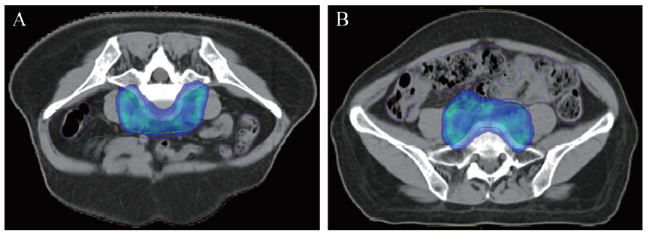

物理师采用Monaco治疗计划系统按照统一参数进行7野逆向动态IMRT计划设计,见图2。X射线射束能量均为6 MV。靶区处方剂量:PTV 45~50 Gy/25 F,1.8~2.0 Gy/F,要求至少95% PTV达到处方剂量,PTV以外不可出现≥ 110%的剂量热点。OAR统一剂量限制。

图2 妇科肿瘤IMRT计划图